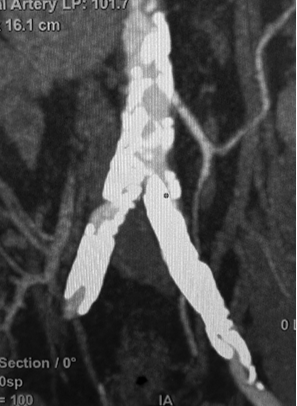

图:术前CT

图:Sterling球囊预扩张(3-150mm、5-100mm)

图:病变远心段(4.9+5.5mm)

图:近心段(5.3+5.6mm)

图:Eluvia药涂支架(6-120mm)

图:支架形态规则处,有效面积24.1mm2,最小径 5.3mm,最大径 5.7mm。

图:支架局部不规整,最小径 3.7mm,最大径 5.7mm

图:术中CT

图:术后CT

图:术后随访